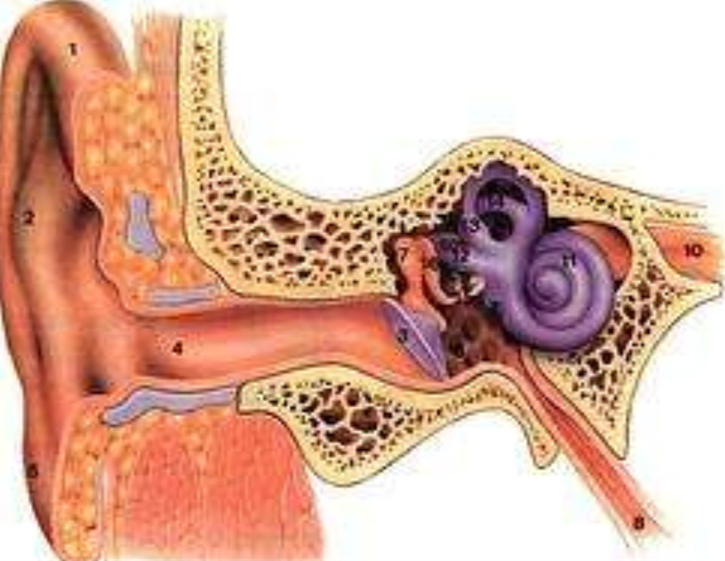

中耳炎圖片

什麼是急性中耳炎

A:中耳炎可能會引起患者出現多種耳部,以及全身的相關症狀,中耳炎的類型不同,所導致的症狀表現也會有所差異。對於常見的急性中耳炎情況,患者會出現突然發作的較為劇烈的耳痛症狀,也可能會同時伴有發熱、頭痛等症狀。部分患者會進一步導致中耳急性化膿性感……